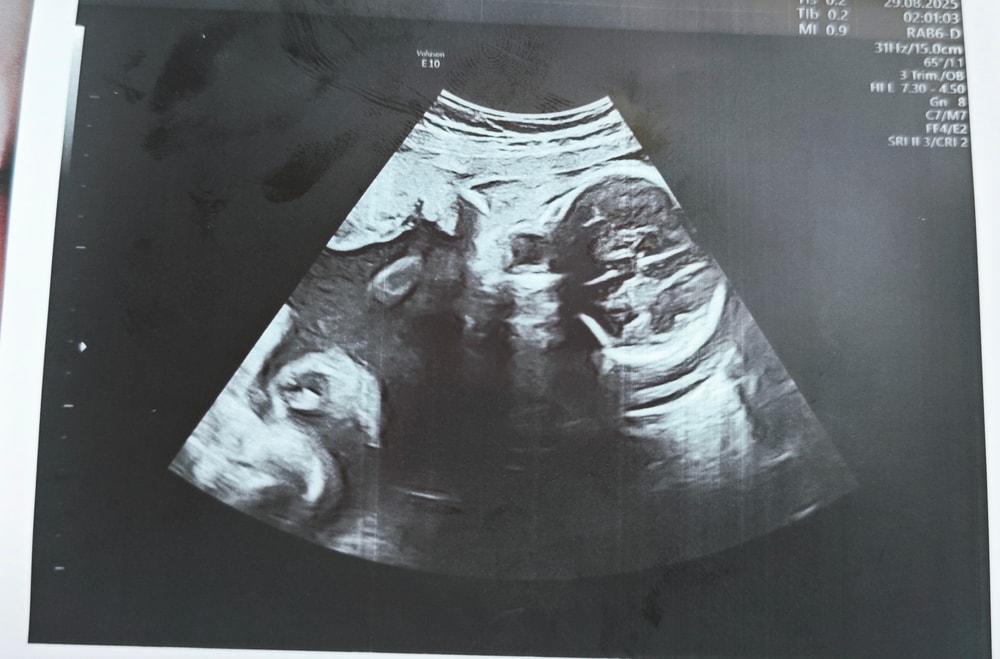

Фото с УЗИ 28 недель

Сходила в частную клинику на УЗИ в 28 недель, сказали, что всё хорошо ттт, и дали фото. И вот когда я уже вышла с клиники и увидела фото, я вообще ничего не поняла. Это вроде голова, но вообще непонятно что где и выглядит жутковато...

Может тут кто-то разбирается или понимает что где на этих фото?

Анастасия , ну а что вы хотели от 2d узи? У вас все ок, видны глазницы. Лобные доли, нос. Сходите на цветное 3d, там черты лица увидите.